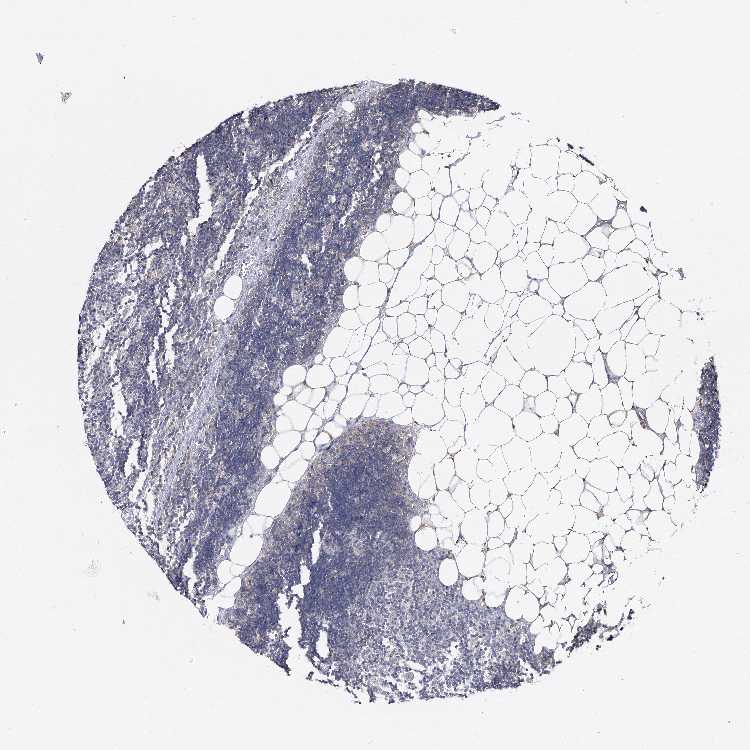

TISSUE PRIMARY DATA LYMPH NODE Show tissue menu

Lymph node

LYMPH NODE - Antibody stainingi

Antibody staining in the annotated cell types in the current human tissue is reported as not detected, low, medium, or high, based on conventional immunohistochemistry profiling in selected tissues. This score is based on the combination of the staining intensity and fraction of stained cells.

Each image is clickable and will lead to virtual microscopy that enables deeper exploration of all samples and also displays staining intensity scores, fraction scores and subcellular localization as well as patient and tissue information for each sample.

Antibody HPA034696Antibody HPA034697Antibody HPA064836

Germinal center cells Not detectedMediumNot detected

Non-germinal center cells Not detectedLowNot detected